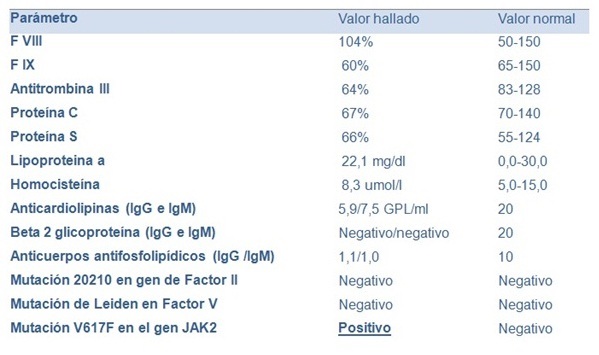

Mujer de 62 años, con antecedentes personales de hipotiroidismo, sin antecedentes de cirugía abdominal, con diagnóstico de síndrome de intestino irritable (episodios repetidos de dolor abdominal, sin síntomas atribuibles a la esfera hepatobiliar, con laboratorio, ecografía y endoscopias digestivas (alta y baja) normales). Consultó por un nuevo episodio de dolor abdominal de características clínicas similares pero con una bioquímica que mostraba una bilirrubina total de 0,62 mg/dl, fosfatasa alcalina de 509 U/l (20-240), gama-glutamil-transpeptidasa de 221 U/l (5-36), aspartato-transferasa de 95 U/l (5-27), alanino-transferasa de 125 U/l (5-33), con proteínas totales 7,30 g/dl, albúmina 4 g/dl, tasa de protrombina 72%, hemoglobina 12,1 g/dl (12,0-15,5), glóbulos blancos 7.9 mil/mm3 (4,3-10), plaquetas 331 mil/mm3 (130-440). La ecografía de abdomen (Figura 1a) mostró un hígado de forma y tamaño habitual, sin alteración de la ecogenicidad, de bordes regulares y sin lesiones focales. La vía biliar intrahepática presentaba leve dilatación y el colédoco proximal medía 9 mm. La vesícula biliar presentaba paredes engrosadas y se encontraba poco distendida a pesar del ayuno. El bazo medía 150 mm de longitud. En el estudio doppler (Figura 1b) no se identificó vena porta permeable, el hilio hepático presentaba varias estructuras vasculares algunas trombosadas, otras con calibre fino que correspondían a la transformación cavernomatosa de la vena porta. Las ramas portales intrahepáticas se encontraban permeables. La arteria hepática estaba aumentada de calibre y tortuosa al igual que sus ramas intrahepáticas. La colangioresonancia magnética mostró (Figura 2): estenosis de tercio medio de colédoco de una longitud aproximada de 2,5 cm, de bordes regulares, con dilatación proximal del colédoco, hilio y vía biliar intrahepática. No se observaba el cístico ni la vesícula biliar. El Wirsung no presentaba alteraciones. La videogastroscopía (VGC) informaba várices esofágicas grandes con puntos rojos que se extendían hacia el cardias y fondo gástrico (GOV-2). Las dosificaciones de CA 19-9 e IgG4 fueron 10,0 U/l (0,0-35) y 291 mg/dl (3,0-201), respectivamente. En la Tabla 1 se detallan los resultados de los estudios de la coagulación. La citometría de flujo en sangre periférica para el diagnóstico de hemoglobinuria paroxística nocturna no constató déficit de glucosil fosfatidil-inositol en las células sanguíneas (monocitos, eritrocitos, granulocitos).

Luego de diagnosticada la colangiopatía portal, es imprescindible el estudio de la causa de la trombosis, por lo que se estudiaron los factores protrombóticos hereditarios y adquiridos. Los neoplasmas mieloproliferativos son la causa más frecuente de trombosis portal en adultos y en este caso se detectó la presencia de la mutación V617 del gen JAK2 apoyando el diagnóstico de Trombocitosis Esencial, sin encontrar otros factores coadyuvantes. En la mayoría de los casos la trombosis portal es de etiología multifactorial y en la Tabla 2 se resumen las etiologías más frecuentes. Es importante tener presente que como consecuencia del hiperesplenismo y la hemodilución, el recuento de células sanguíneas frecuentemente es normal. El recuento plaquetario por encima de 200 mil en un paciente con esplenomegalia e hipertensión portal, lleva a la sospecha de un síndrome mieloproliferativo como es el caso de la paciente que se detalla. Se inició anticoagulación previa ligadura endoscópica de las várices esofágicas. En la evolución se mantuvo asintomática y se constató normalización del hepatograma sin mediar tratamiento específico.